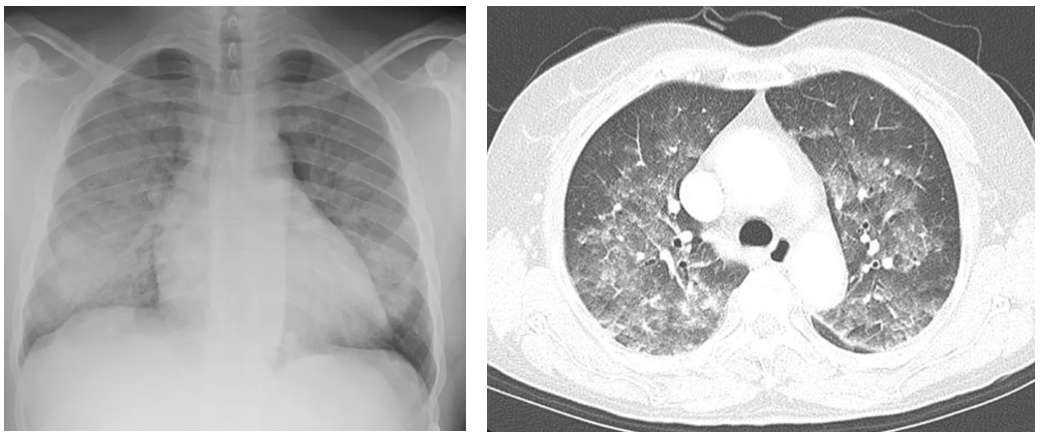

(2) CXR: Diffuse alveolar opacity

(3) CT: Bilateral GGO or patchy consolidation